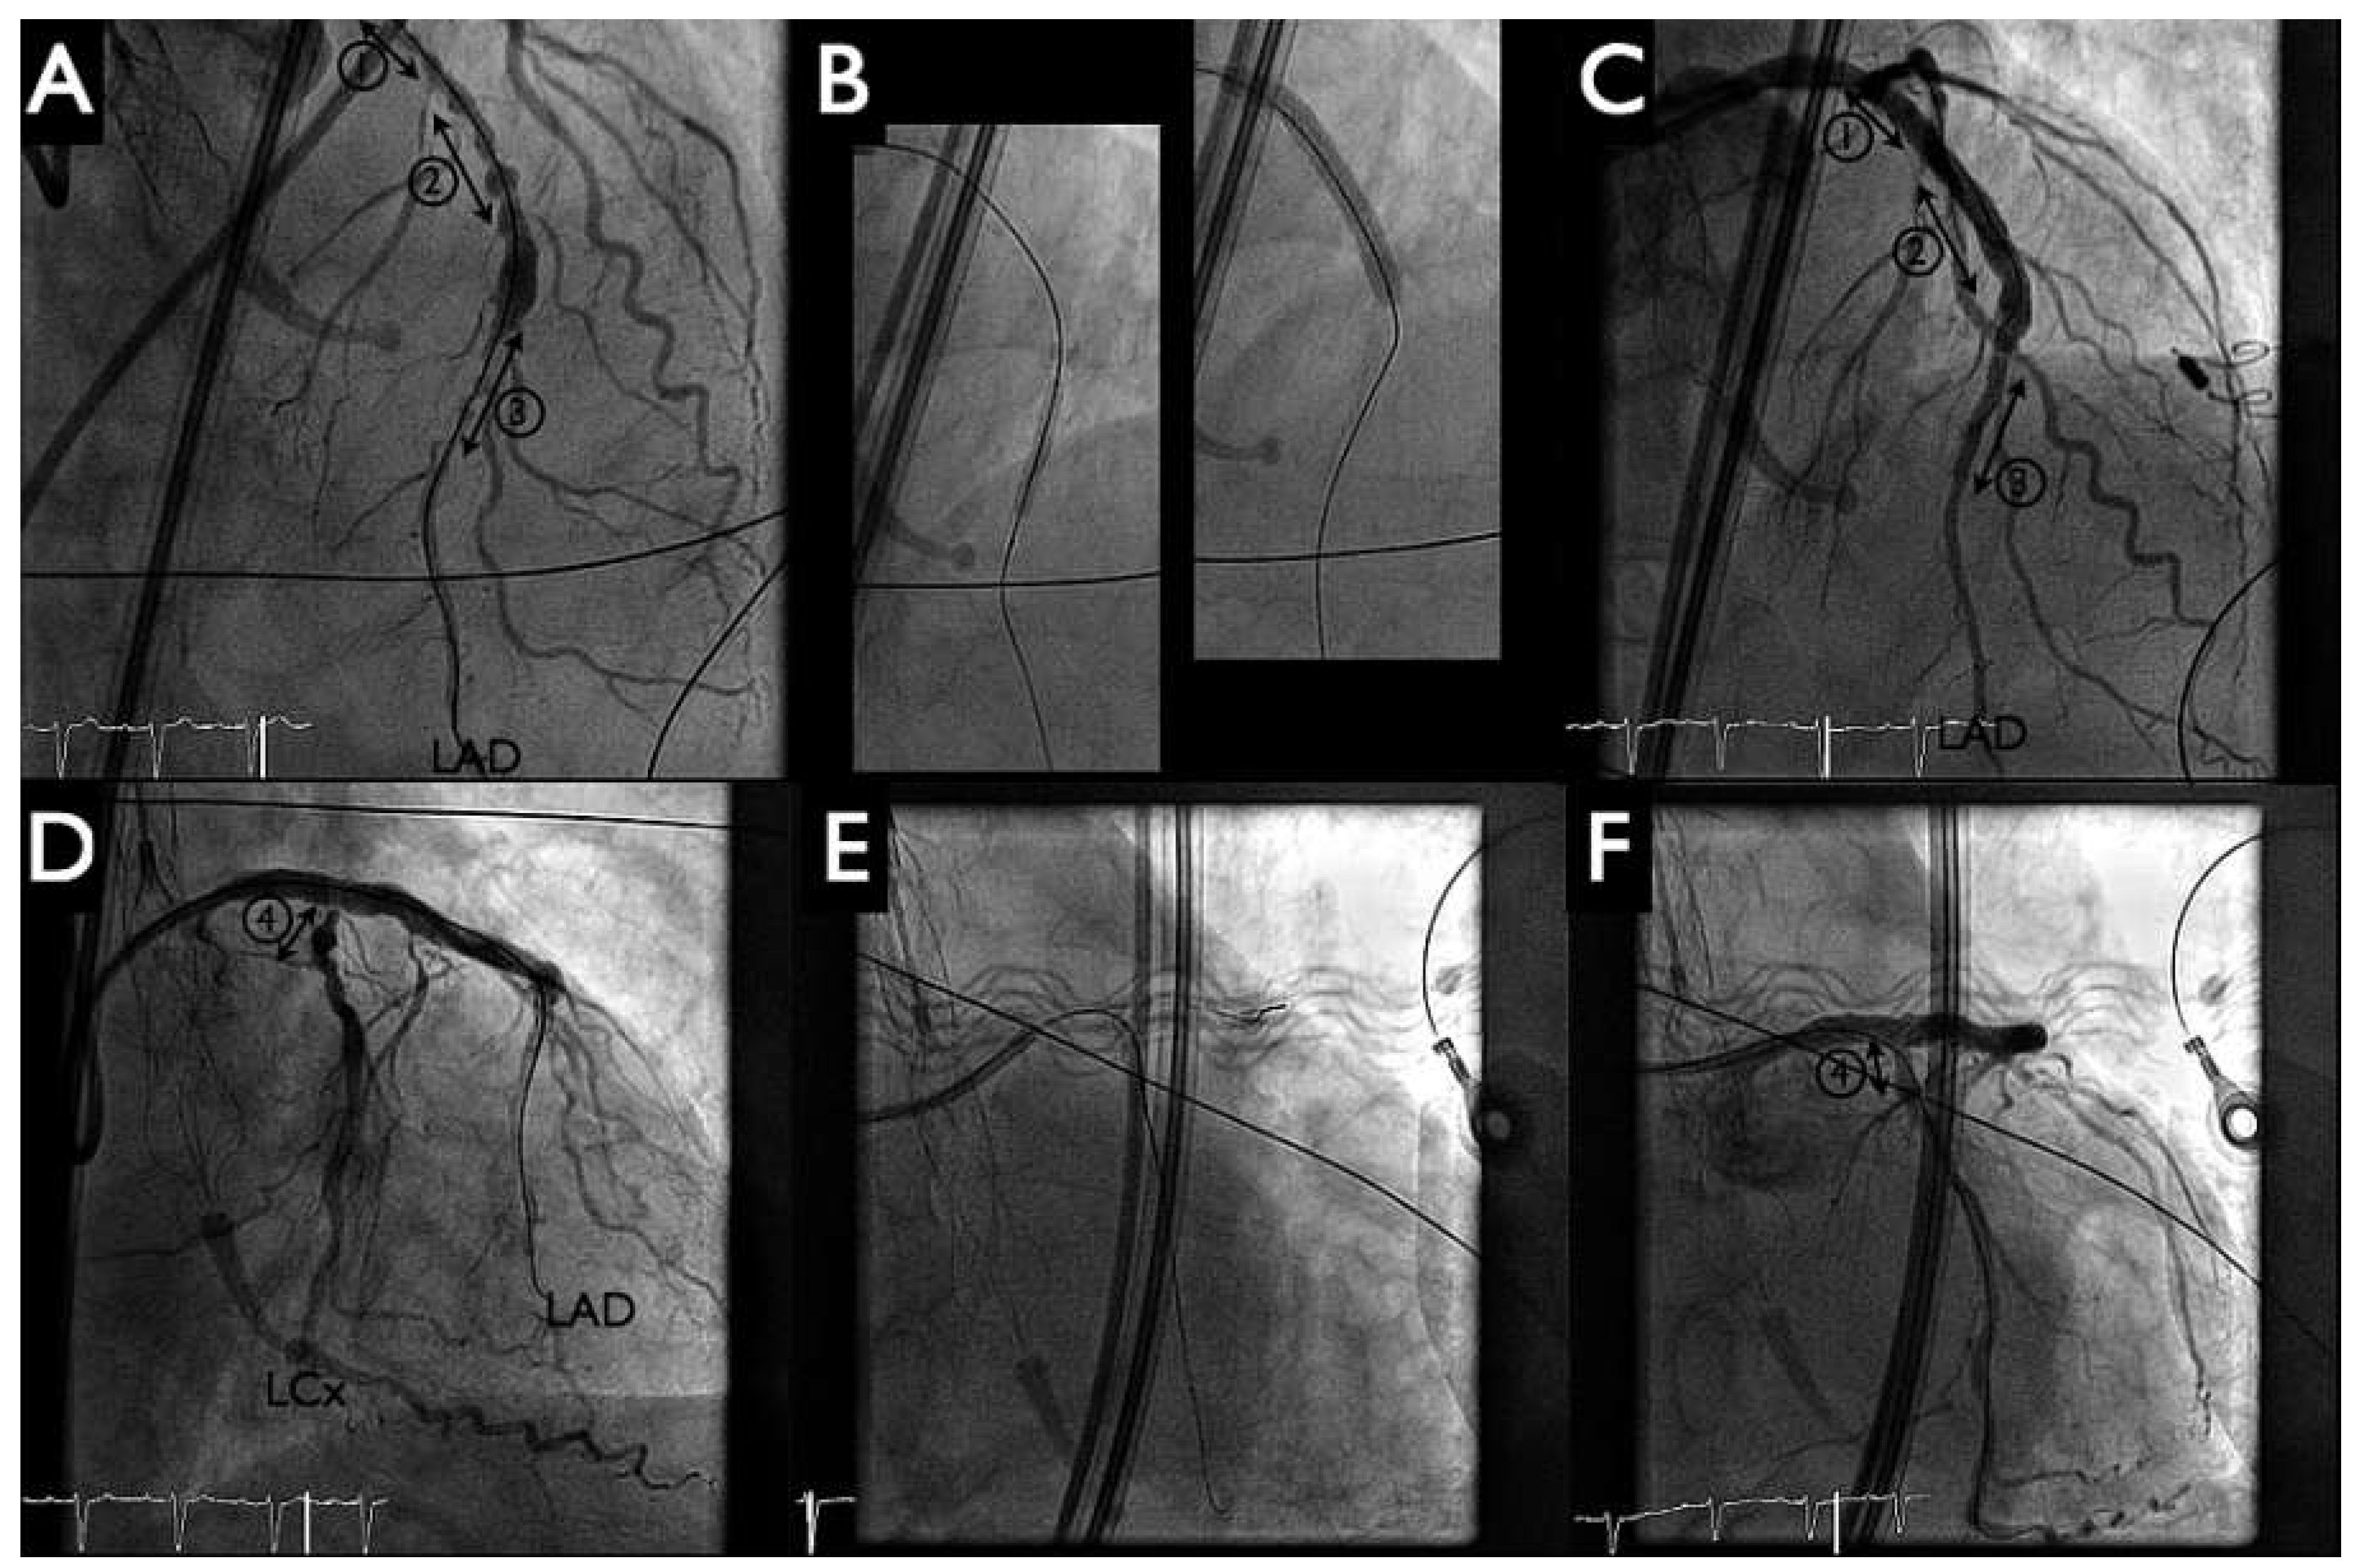

Figure 4. Percutaneous coronary intervention. Panels A–C: The three (lesions 1–3) left main to proximal left anterior descending (LAD) were treated with balloon angioplasties and implantation of two drug-eluting stents. Panels D–F: ostial circumflex artery (LCx, lesion 4) was treated by implantation of a third drug-eluting stent and kissing-balloon inflation. Good final results (panels C, F).

Following this, the pigtail catheter was exchanged for a 6 Fr Q4 guiding catheter with PCI of the distal left anterior descending artery (LAD) (SYNERGY II 2.25–20 mm, Boston Scientific, Figure 4 panel B left) and proximal LAD to distal left main artery (SYNERGY II 4.00–38 mm, Boston Scientific, Figure 4 panel B right) with T-stenting into the left circumflex artery (SYNERGY II 2.75–12 mm, Boston Scientific, Figure 4 panels B, E). Postdilatation with kissing balloon inflation (4.00–15 mm in LAD, 2.75–12 mm in the left circumflex artery) demonstrated a good final angiographic result (Figure 4 panels C, F). During the intervention no significant haemodynamic changes were noted, and the patient tolerated the balloon inflations well. The HeartMate-PHP was then gently removed into the descending aorta. The pump was stopped and the conduit could be easily resheathed into the catheter (Figure 5 panels A, B). Haemostasis was achieved with tightening of the two Perclose (Figure 5 panel C) and the patient was given a loading dose of 60 mg prasugrel.